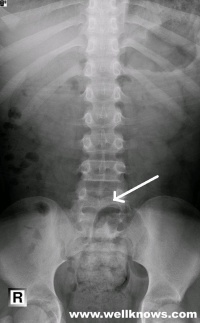

X线照片、CT 与MRI 扫描显示椎管畸形,棘突及椎板缺损,有助于疾病的诊断。

无脊髓或神经根受累者可长期无症状。有症状者症状也多于10~15岁后出现。症状程度则据脊髓和神经根发育异常和受压迫、受牵扯的程度而定。病人常诉下肢无力,行走困难,足变形,下肢及会阴部鞍区感觉异常膀胱肛门括约肌功能障碍,反复发生泌尿系感染,肌肉萎缩等。有时有腰痛。检查发现下肢及足力弱、踝反射消失、跟腱紧、足弓高、下肢及鞍区感觉障碍,肛门括约肌松弛。双下肢可不等长,双足不等大,或见足畸形等。脊柱 X射线平片可明确诊断。无症状者常在体检或因其他疾患而拍脊柱 X射线片时发现。神经系症状严重者,则需行脊髓造影、CT或磁共振检查以了解椎管内的情况,以便于及时处理。